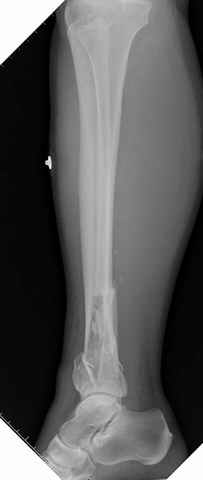

На снимках варианты фиксации малоберцовой:

№ 1 двух лодыжек